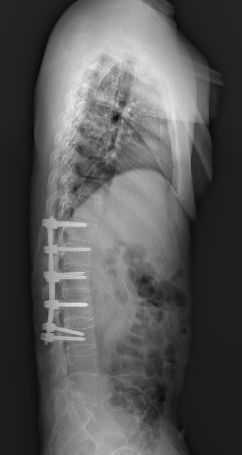

全脊柱正侧位显示骶髂关节间隙消失

脊柱竹节样融合改变

术后复查见腰1、腰2椎体高度恢复,螺钉位置满意